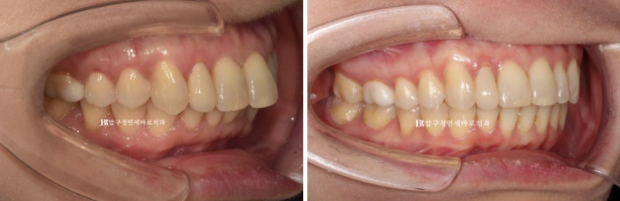

치료 전 후 보겠습니다.

좌 - 치료 전 / 우 - 치료 후

치간삭제를 통한 앞니 돌출감 개선

24.02~24.12

앞니 배열 개선과 가위교합 개선